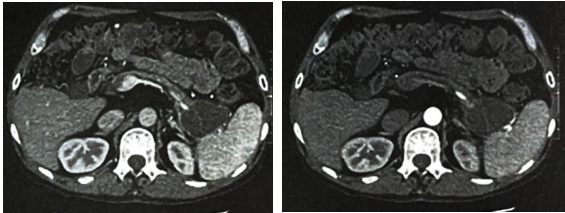

腹部CT结果显示(图1):①胰腺萎缩,胰尾低密度影,结合病史,考虑假性囊肿;②肝Ⅵ段钙化灶;③胆囊结石,胆囊炎可能。

图1. 腹部CT